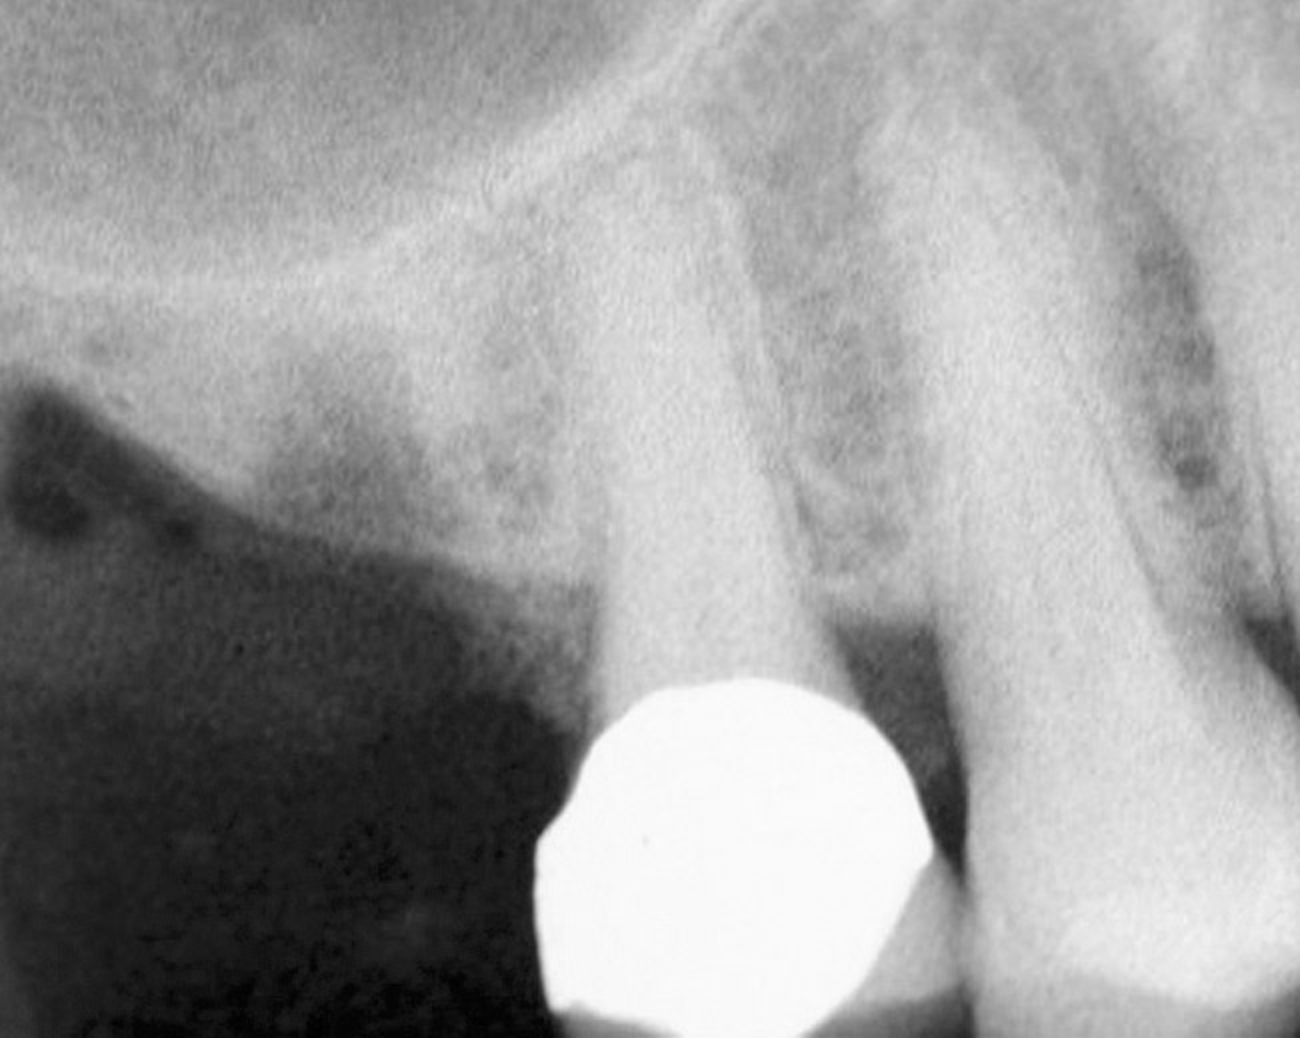

Figure 14  Additional bone was added via the osteotomy.

Figure 14

Figure 15  Implant successfully placed.

Figure 15